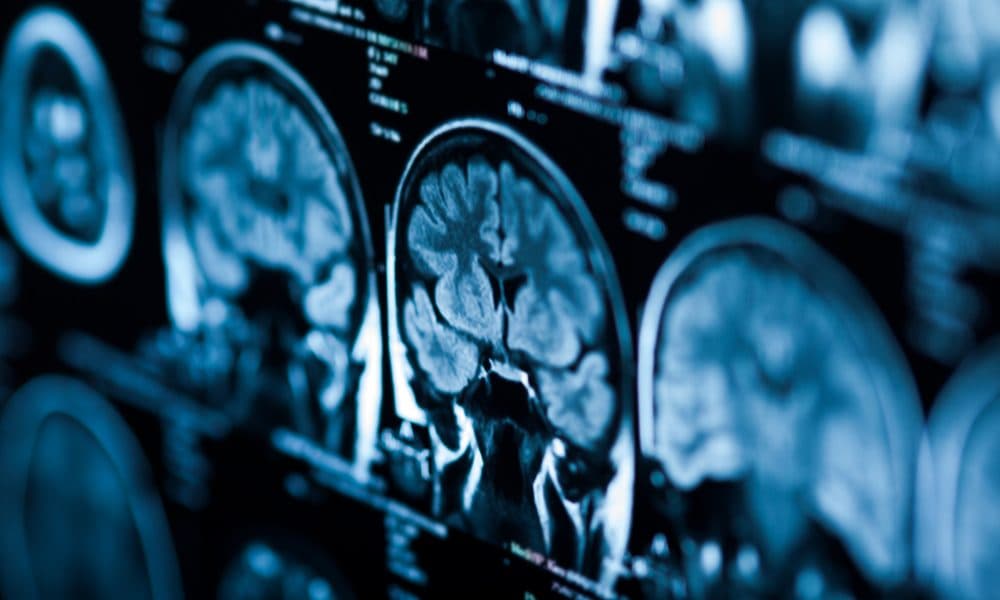

Drugs developed to combat HIV and AIDS are being trialled for the first time in patients with multiple brain tumours.

The rare inherited genetic condition causes tumours such as schwannoma (which include acoustic neuroma), ependymoma and meningioma which develop on the membrane surrounding the brain.